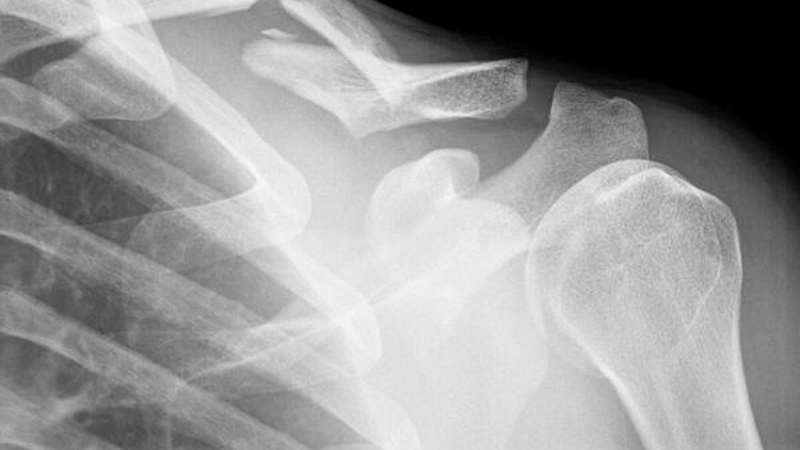

La Habana, 30 nov.- Un taller sobre el control de la calidad en radiología médica sesionó este martes en esta capital, con el auspicio del Centro de Protección e Higiene de las Radiaciones (CPHR), radicado en la vecina provincia de Mayabeque.

El mejoramiento de la seguridad y la atención al paciente en el país fue el tema central del encuentro en el Hotel Comodoro, de acuerdo con el programa del evento al que tuvo acceso la Agencia Cubana de Noticias.